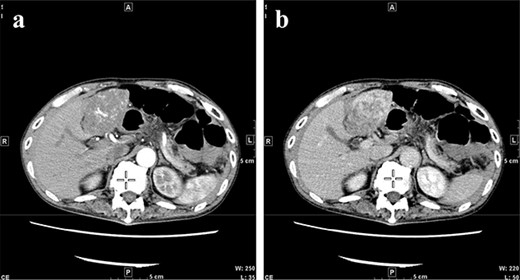

A 77-year-old man was referred to the Department of Gastroenterology at our hospital for suspicion of hepatocellular carcinoma and cancerous peritonitis. He was scheduled to be hospitalized for a thorough examination at a later date. However, 3 days after his first visit, he returned to the Emergency Department with a complaint of abdominal distension. He was hospitalized on the same day with a diagnosis of intra-abdominal bleeding due to a ruptured tumor in the lateral section of the liver. Computed tomography (CT) and magnetic resonance imaging (MRI) revealed a tumor with a maximum diameter of 8 cm in the lateral hepatic region and ascites around the liver and in the pelvic floor. Dynamic CT showed blood vessel-like early staining inside the tumor, and the contrast effect gradually enhanced (Fig. 1). During gadolinium ethoxybenzyl diethylenetriamine pentaacetic acid-enhanced MRI, this contrast effect gradually increased from the peripheral part toward the hepatocyte phase from the arterial phase (Fig. 2). Levels of tumor markers (alpha-fetoprotein, protein induced by vitamin K absence or antagonist-II, carcinoembryonic antigen and carbohydrate antigen 19–9) were within the normal range (Table 1). Based on the imaging findings, a diagnosis of spontaneously ruptured hepatic hemangioma was made. Since the patient’s general condition was stable and there were no findings suggestive of active bleeding, he decided to undergo elective surgery. Thus, he was not requested to continue being hospitalized and was discharged. Six days after discharge, he was transported to the emergency room in a state of shock and was hospitalized the same day. With the diagnosis of hemorrhagic shock due to re-rupture of the liver tumor (Fig. 3), emergency transarterial embolization (TAE) was performed. No apparent extravasation was observed on angiography, and A3 was embolized. Seven days later, he underwent left lateral hepatic segmentectomy. The postoperative course was generally good. The post-ruptured tumor was found in the left lateral segment, the cut surface was white, the edges were brown and the boundaries were unclear (Fig. 4). Histopathological examination revealed that sections of the white and brown parts of the margin were viable tumors, showing highly atypical spindle-shaped cells, arranged like sinusoidal vessels and partly solid, and there were many mitotic figures. There was no capsule, and the tumor infiltrated the surrounding liver parenchyma (Fig. 5a–c). Immunostaining showed CD31 (+), CD34 (partially positive), CK-CAM5.2 (−), α-SMA (−), HMB45 (indeterminate) and p53 (+), and the patient was diagnosed with hepatic angiosarcoma (Fig. 5d). Fever was observed 21 days after surgery, and CT was performed, revealing multiple masses in the liver (Fig. 6a). Another CT scan was performed 27 days postoperatively, which suggested that the liver masses were rapidly increasing; hepatic angiosarcoma recurrence was then confirmed (Fig. 6b). The patient requested the best supportive care at home and was discharged 31 days after the operation. He died at home 36 days after surgery.

(a) CT on Day 21 after surgery. Multiple tumors are found in the liver. (b) CT re-examination performed 27 days after the operation shows multiple rapidly increasing liver masses. CT, computed tomography.